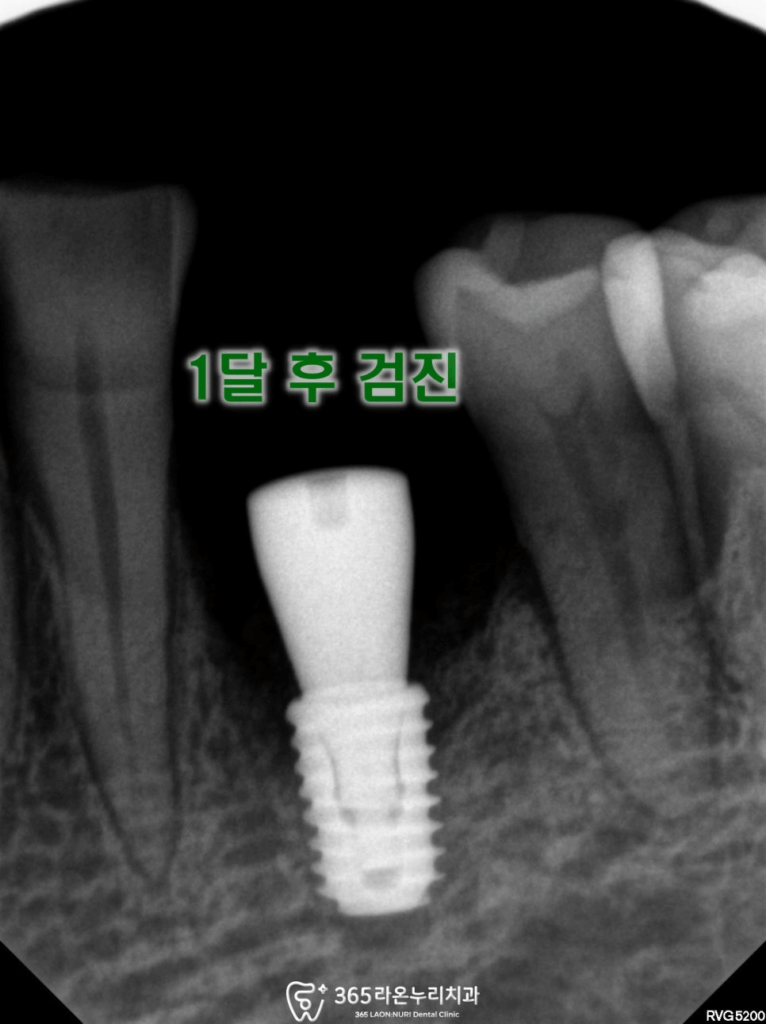

골유착 하는 동안 나머지 치아는

잇몸치료 및 치주관리를 하면서

식립 한 부위를 체크 합니다.